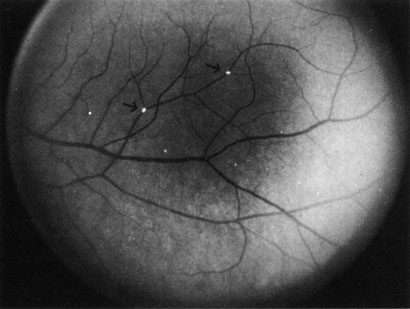

Cilioretinal arteries can be selectively obstructed (Fig. 3). More commonly, however, they occur in association with central retinal vein obstruction.113 When they supply a significant portion of the macula, decreased visual acuity is common. Prognosis for visual outcome in such patients is good. Brown and co-workers114 studied 10 eyes having an isolated cilioretinal artery obstruction. Of those, 60% had an initial visual acuity of 20/40 or better and on follow-up examination, all eyes but one had a best-corrected visual acuity of 20/40 or better.114